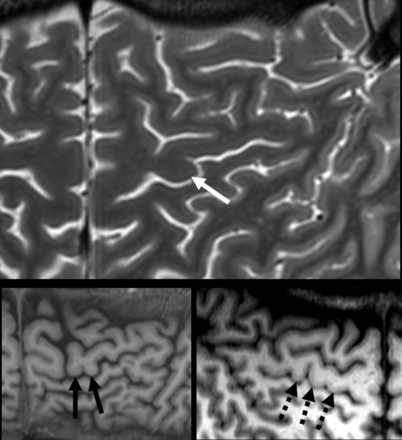

Variants of the handknob. In our study, we only considered the inverted Ω shape (white arrow) because other variants, such as inverted ε (continuous black arrows), and multiple bulgings (dotted black arrows) were not assessed.